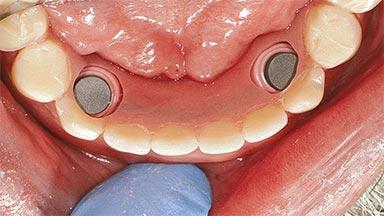

Improving an Existing Implant-supported Denture in an Alzheimer Patient with Bipolar Affective Disorder with Moderate Depression and Dementia

An 83-year-old man presented together with his caregiver at the dental department of the Medical University of Innsbruck, Austria with complaints of swelling in the right maxillary canine area and loss of retention of his 5-years-old mandibular denture. The patient had a significant medical history (20 years) of bipolar affective disorder with moderate depression (F 31.3) and dementia in Alzheimer’s disease (F 00.2). The patient had been in ambulant psychiatric therapy for his depressive illness for the past 20 years. He lived alone and had no children; his sister assisted with daily living. She reported that the patient exhibited compulsive hoarding behavior. In the previous two months, she had noted increasing disorientation and vertigo in the patient. She therefore accompanied him for a medical consultation at the Department of Psychiatry and Psychotherapy of the Medical University of Innsbruck. He was released home after a 6-week inpatient stay.

# of Implants 2

Type of Implants One-Piece

Attachment One-Piece

Defining Characteristics Fully edentulous lower jaw to be rehabilitated with an implant-borne removable overdenture